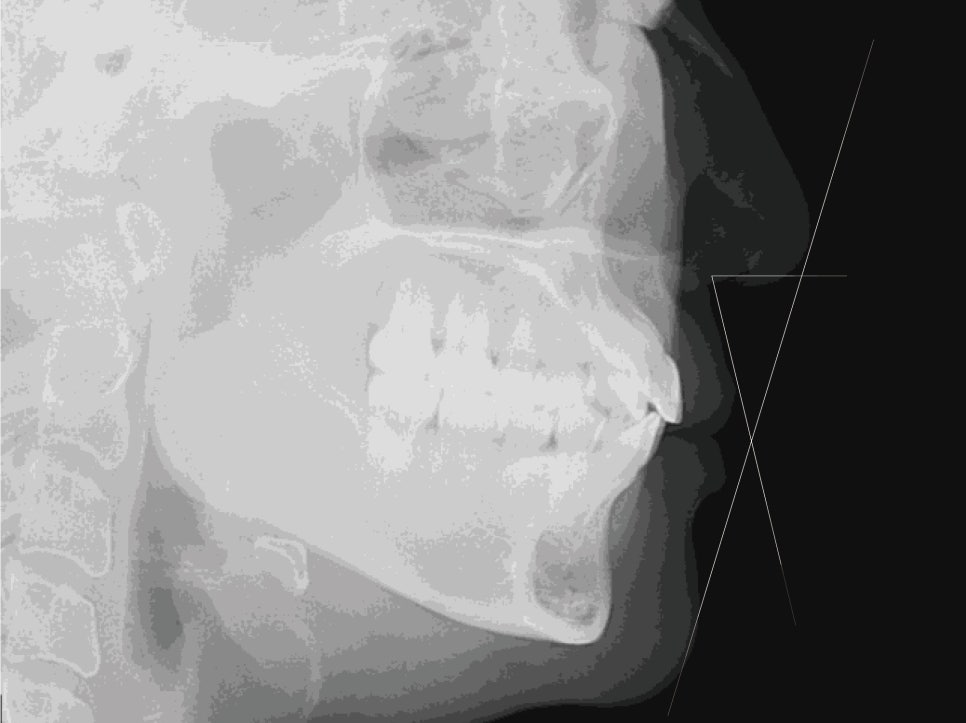

-Tx plan-

CC: 앞니 덧니

상악 6전치/하악6전치

투디교정장치

치간삭제(IPR)

상악 제1대구치에 Bite raise(일시적)

2D(투디)교정 앞니덧니,반대교합 치아교정